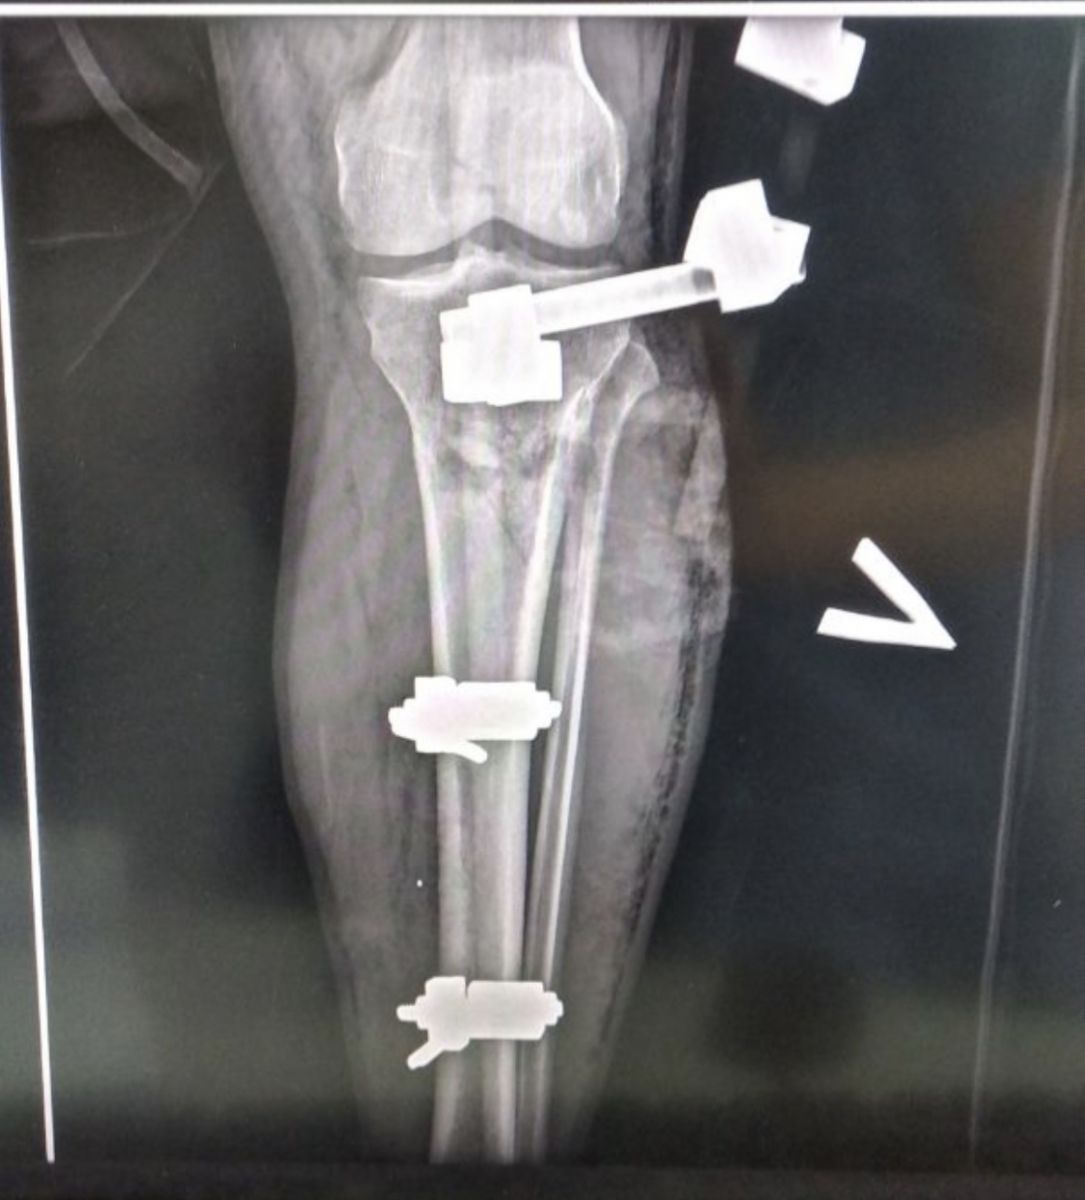

У бою під Роботиним захисник отримав важкі ураження обох ніг. До лікарні його доправили з уламковим пораненням, подвійним вогняним відкритим перелом лівої гомілки. Витягти вороже залізо з його правої ноги лікарям поки не вдалось.

Михайлові вже зробили кілька операцій, та, на жаль, то лише початок тривалого і складного одужання. Допоки не загояться рани, хірурги кістки не чіпають. Разом із чоловіком проходять нелегкі випробування і дружина з маленькою донечкою. Дівчинка народилась на другий день кривавого вторгнення, а за рік її тато сам став до армійських лав.